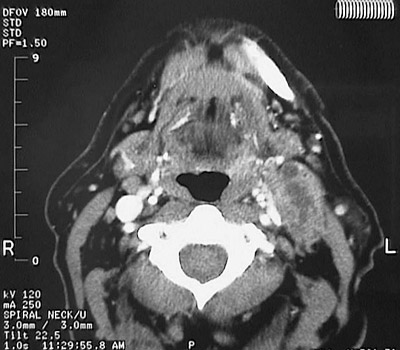

![]() | In the axial CT scan view seen here, a squamous cell carcinoma has extended into soft tissues on the right from the posterior base of the tongue, occluding the jugular vein. There is extensive central necrosis in the mass of tumor extending to the right. |